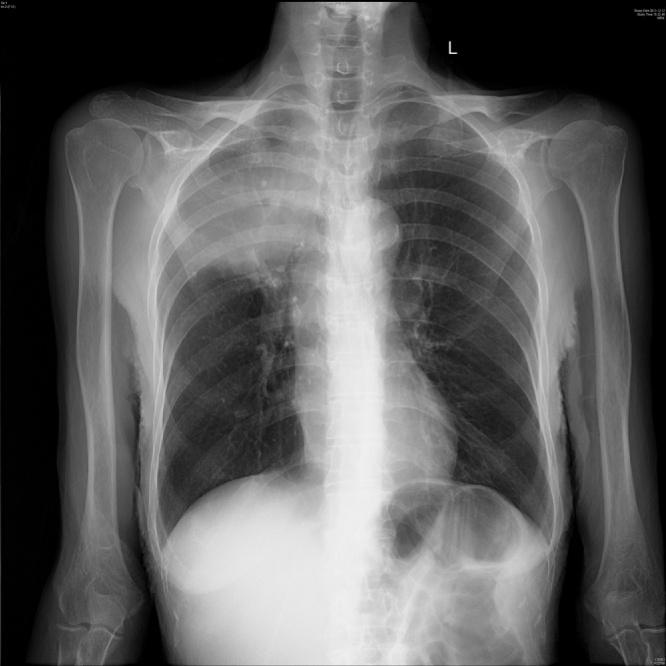

The purpose of this case is to investigate a case of obturator hernia leading to right thigh abscess on 68-year-old woman of China. A 68-year-old Chinese woman was referred to China-Japan Friendship Hospital of Jilin University with abdominal pain, bloating, exhaust, stop defecation in 2011. She had chronic bronchitis, emphysema with a history of 20 years. This patient did not have any bad habits, such as smoking, alcohol consumption, etc. In this surgery, CT was used to diagnose the basic condition of the patient. Surgery was used for treatment of patients with diseases. In addition, this operation was performed by the china-Japan Friendship Hospital of Jilin University. The results of this case showed that the cervix of rectal right anterior wall can hit a funicular neoplasm, toughening, smooth, with tenderness, considering for the external pressure bowel loops. The inside of the right thigh showed obvious swelling, skin slightly bruising, and tenderness. Chest radiographs showed that patients had emphysema, multiple planes of fluid and air in the abdomen. Patients had been successfully operated, but she died because of severe infection.

本病例的目的是调查一名68岁中国女性因闭孔疝导致右大腿脓肿的病例。一名68岁的中国女性于2011年因腹痛、腹胀、排气、停止排便被转诊至吉林大学中日联谊医院。她有20年慢性支气管炎、肺气肿病史。该患者没有吸烟、饮酒等任何不良习惯。在此次手术中,使用CT诊断患者的基本病情。采用手术治疗该患者的疾病。此外,此次手术由吉林大学中日联谊医院实施。该病例结果显示,直肠右前壁宫颈可触及条索状肿物,质韧,表面光滑,有压痛,考虑为肠管外压。右大腿内侧明显肿胀,皮肤轻度瘀斑,有压痛。胸部X线片显示患者有肺气肿,腹部有多个气液平面。患者手术成功,但因严重感染死亡。